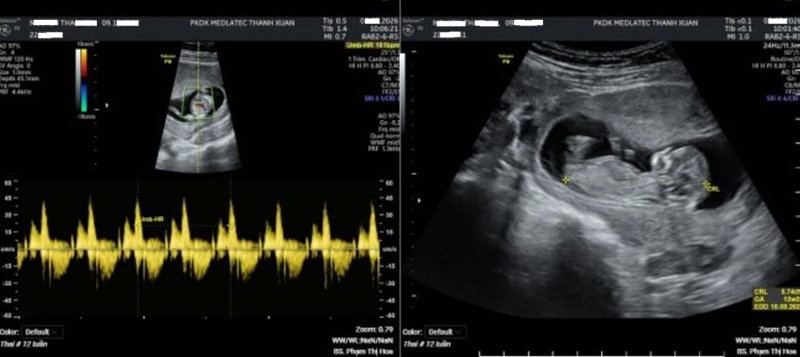

Kết quả siêu âm thai 4D ghi nhận một thai 12 tuần 2 ngày, tim thai 161 lần/phút, chưa phát hiện bất thường về hình thái. Tuy nhiên, chỉ số PI động mạch tử cung trái là 2.27 và bên phải là 1.67 – những thông số có ý nghĩa trong đánh giá nguy cơ tiền sản giật.

Kết quả siêu âm thai của thai phụ